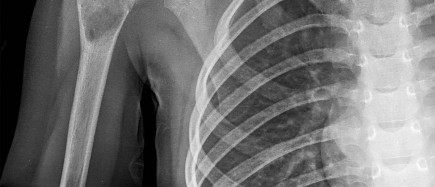

An 19-year-old male presents to the emergency room following an motor vehicle accident as an unrestrained driver. Examination reveals unilateral jugular vein engorgement. Chest and special view

radiographs are seen in Figures A and B respectively. Following CT scan of the chest, the next step in management is